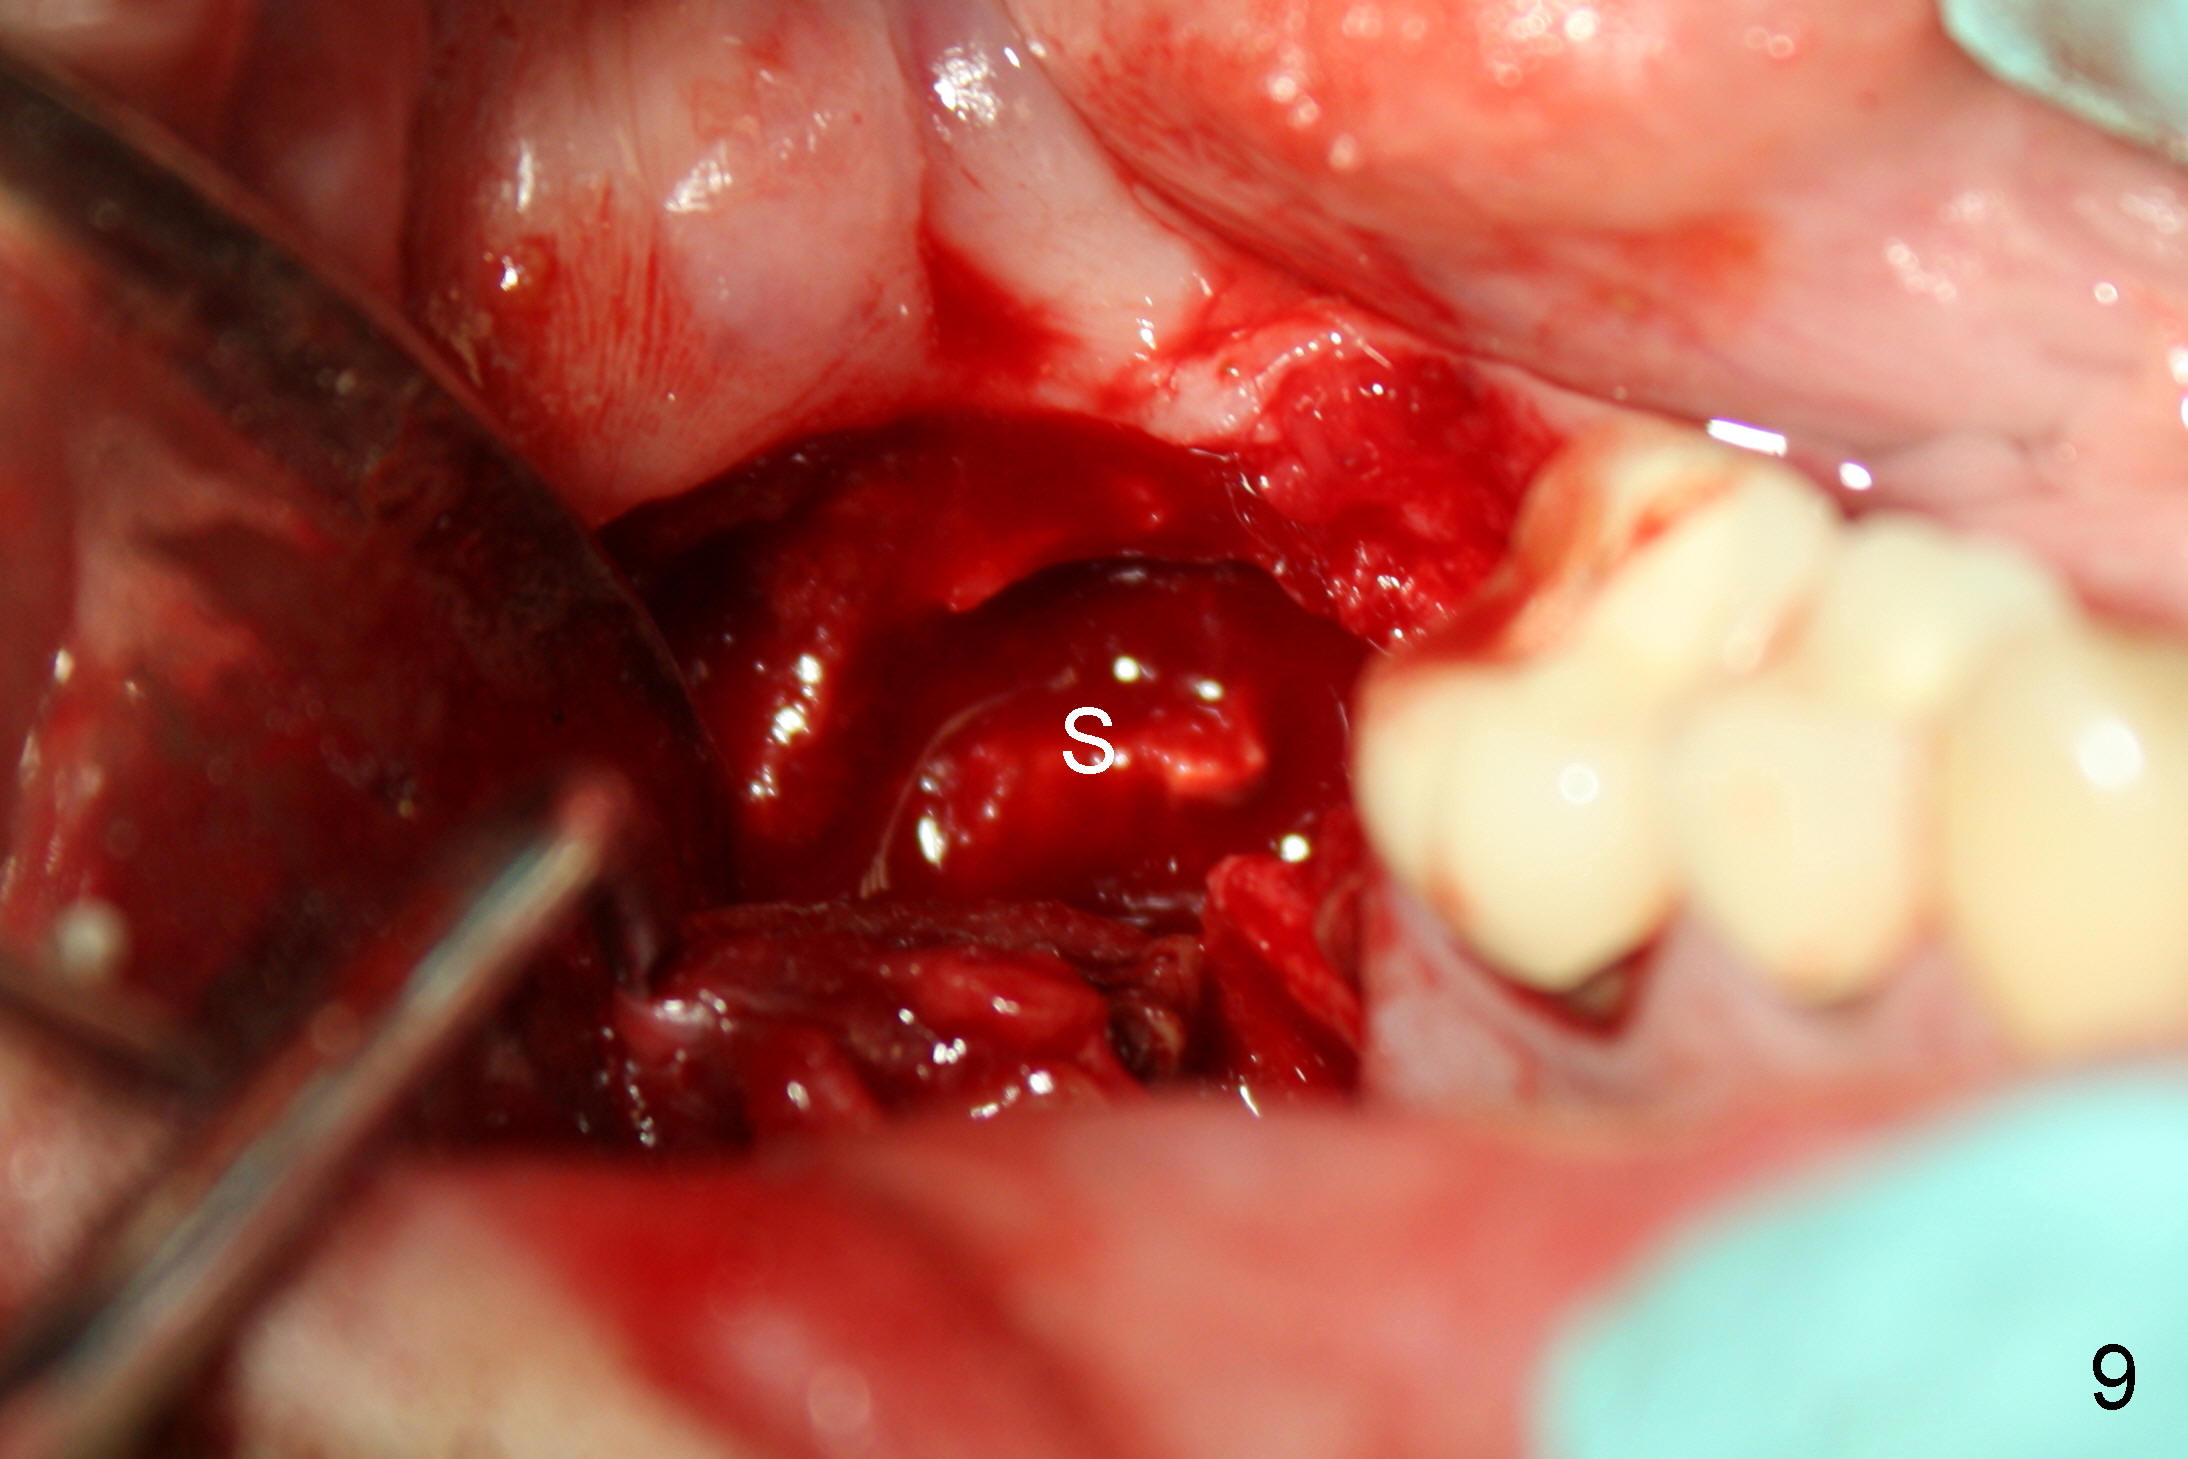

confirmed (Fig.8). Extraction of #31 shows the septum (Fig.9).

Then the